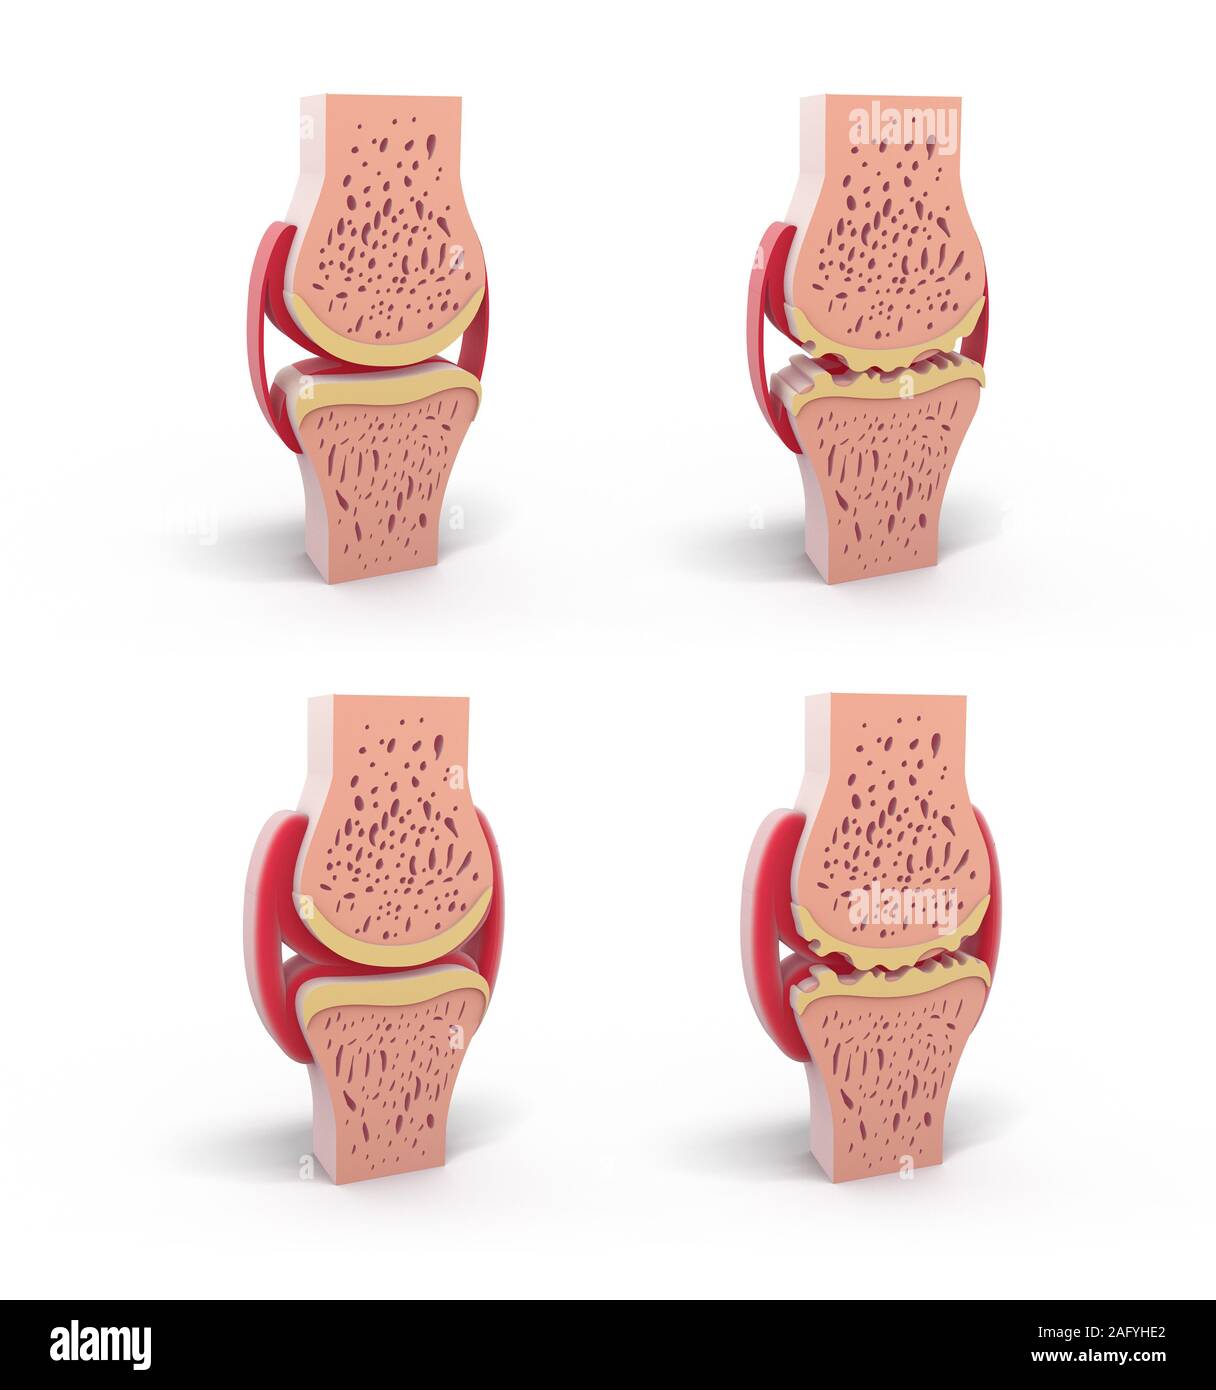

3d illustration of healthy and spherical synovial joint. In four representations standing and isolated on white background. Stock Photohttps://www.alamy.com/image-license-details/?v=1https://www.alamy.com/3d-illustration-of-healthy-and-spherical-synovial-joint-in-four-representations-standing-and-isolated-on-white-background-image336823258.html

3d illustration of healthy and spherical synovial joint. In four representations standing and isolated on white background. Stock Photohttps://www.alamy.com/image-license-details/?v=1https://www.alamy.com/3d-illustration-of-healthy-and-spherical-synovial-joint-in-four-representations-standing-and-isolated-on-white-background-image336823258.htmlRF2AFYHE2–3d illustration of healthy and spherical synovial joint. In four representations standing and isolated on white background.